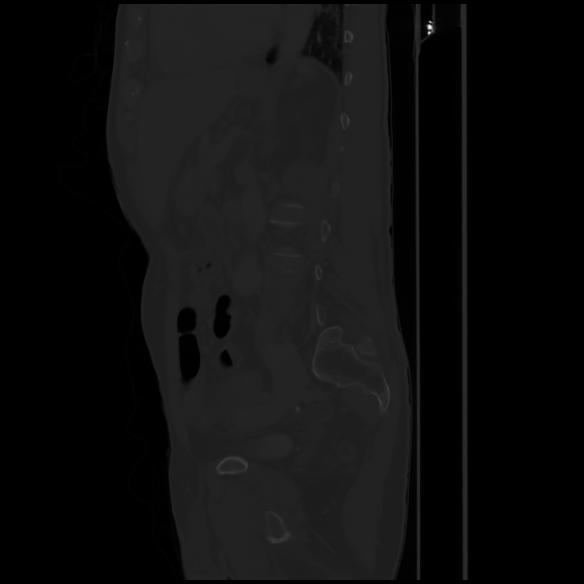

7 CUERPO,CE,Sagittal,3.000,CUERPO,Sagittal,